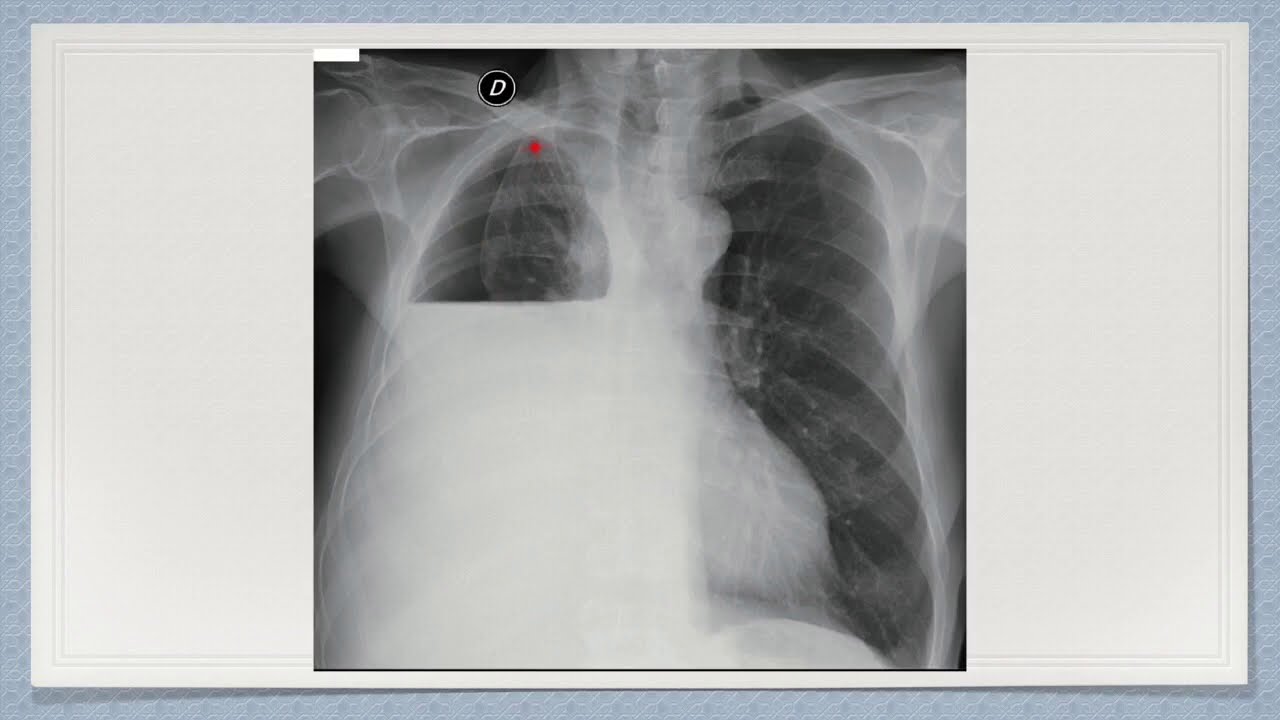

La acumulación de pus en la cavidad pleural, también conocida como empiema pleural, es una condición médica grave caracterizada por la acumulación de pus, un líquido infectado, en el espacio entre las membranas que recubren los pulmones y la pared torácica. Esta acumulación puede ser causada por infecciones bacterianas, traumas torácicos o enfermedades subyacentes.

El tratamiento para el empiema pleural generalmente implica drenaje del pus acumulado mediante procedimientos como toracocentesis o colocación de tubos torácicos para drenaje continuo. Además, se recetarán antibióticos para tratar la infección subyacente. En casos graves, puede ser necesaria la cirugía para limpiar la cavidad pleural.